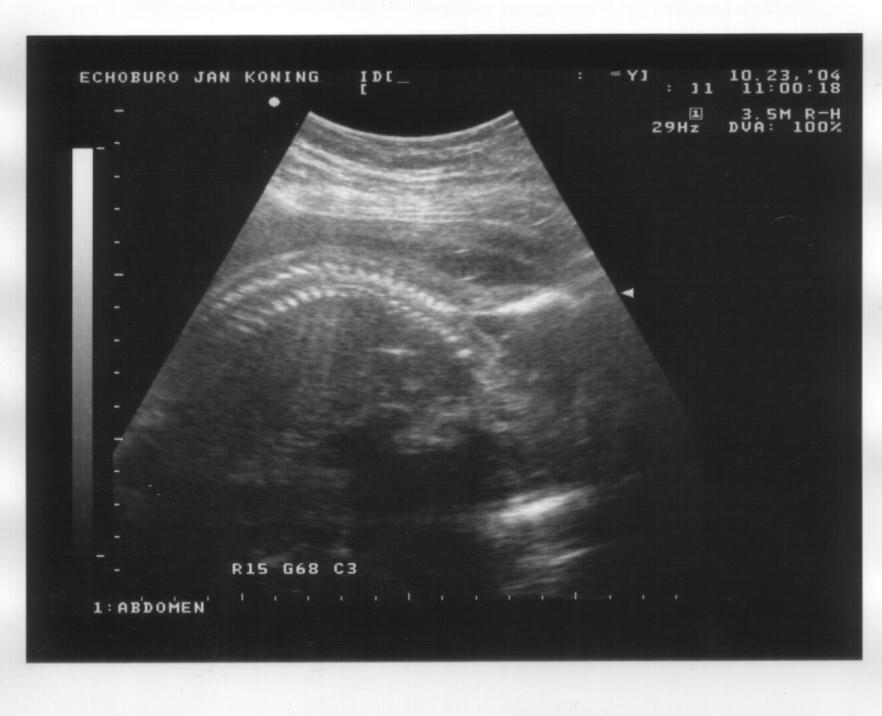

23 oktober 2004

Links: Zijaanzicht, waarbij het voorovergebogen ligt. Ruggewervel goed te zien